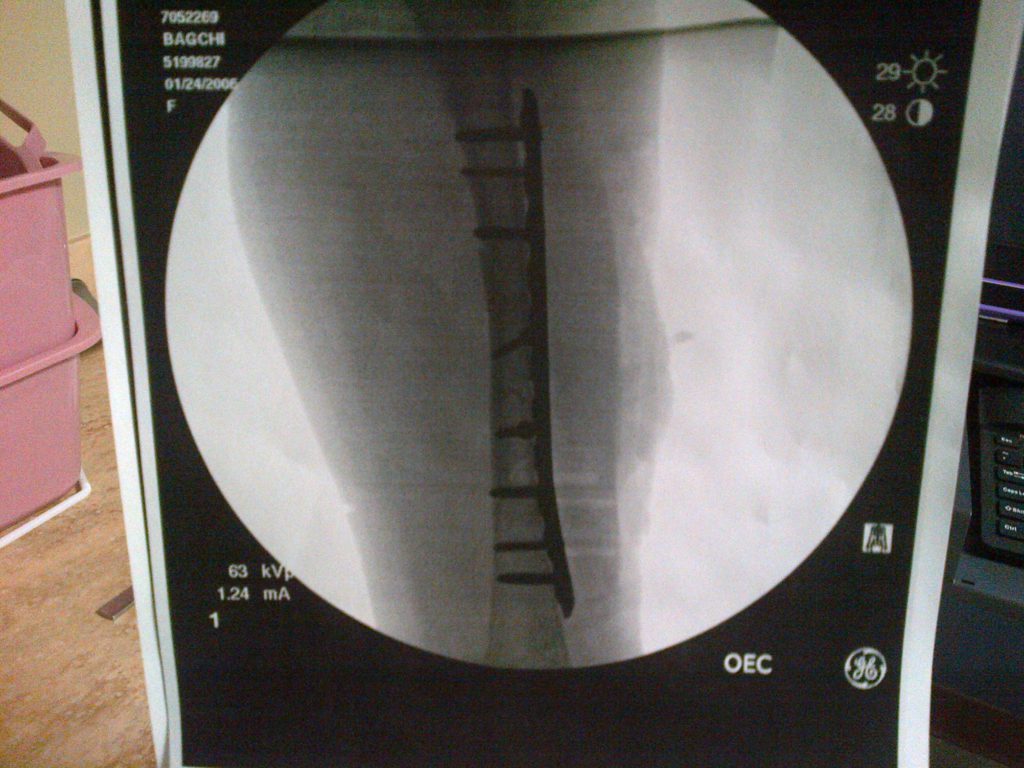

I've always loved to play sports. My main sport is soccer and I play 4 days a week 10 months a year and I also play on a travel basketball team. But I love just about any sport - tennis, skiing, waterskiing, baseball... I really love it all. On Super Bowl Sunday February 1st 2015 right after my 9th birthday, I went skiing with my Daddy. I was skiing down the mountain when I was pushed by another skier accidentally and ended up colliding with an unpadded metal pole in the ski run. Ouch! I was rushed to a trauma center with a severely shattered femur which needed emergency surgery to repair including putting a metal plate and 8 screws in my leg. I had a bunch of other complications and spent a while in the trauma center. After that I came back to New York City and was treated by Dr. Widmann. I was so used to doing so many sports and first I couldn't move then just walking was hard. I remember trying to move my leg a few inches took me a long time. I recovered from the break, but walked and ran with a limp and couldn't do what I used to on and off the field which made me sad. Over the course of the next year-and-a-half I have had surgery to remove the metal plate and 8 screws in my leg - Dr. Widmann did a great job - and had extensive rehabilitation as well as treatment for the scar. Some doctors had told me in the trauma center that I would never walk normally again but I didn't give up. Dr. Widmann help me regain my confidence and my physical therapist Josh was a rock star. I am back playing soccer, tennis, basketball and just went skiing for the first time in nearly two years since my accident. Everyone at Hospital for Special Surgery was nice, built my confidence, and gave me the best care. While I still have a big scar that reminds me of what happened, I'm stronger because of the experience. Nothing will stop me now! Thank you to everyone at HSS and especially to Dr. Widmann. Love, Caroline